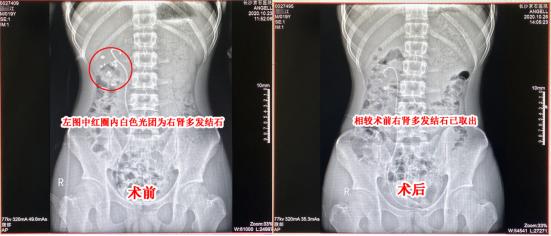

小江术前术后腹平片对比图

10月16日,小江顺利接受了Ⅰ期双镜联合微创保肾取石术,术中突破了结石极为分散、积水严重、感染随时可能扩散等多重难关,顺利引流积水并清除了大部分结石。待小江恢复一段时间达到手术标准后,24日小江接受了Ⅱ期碎石清石术,至此,结石和积水危机全部解除。